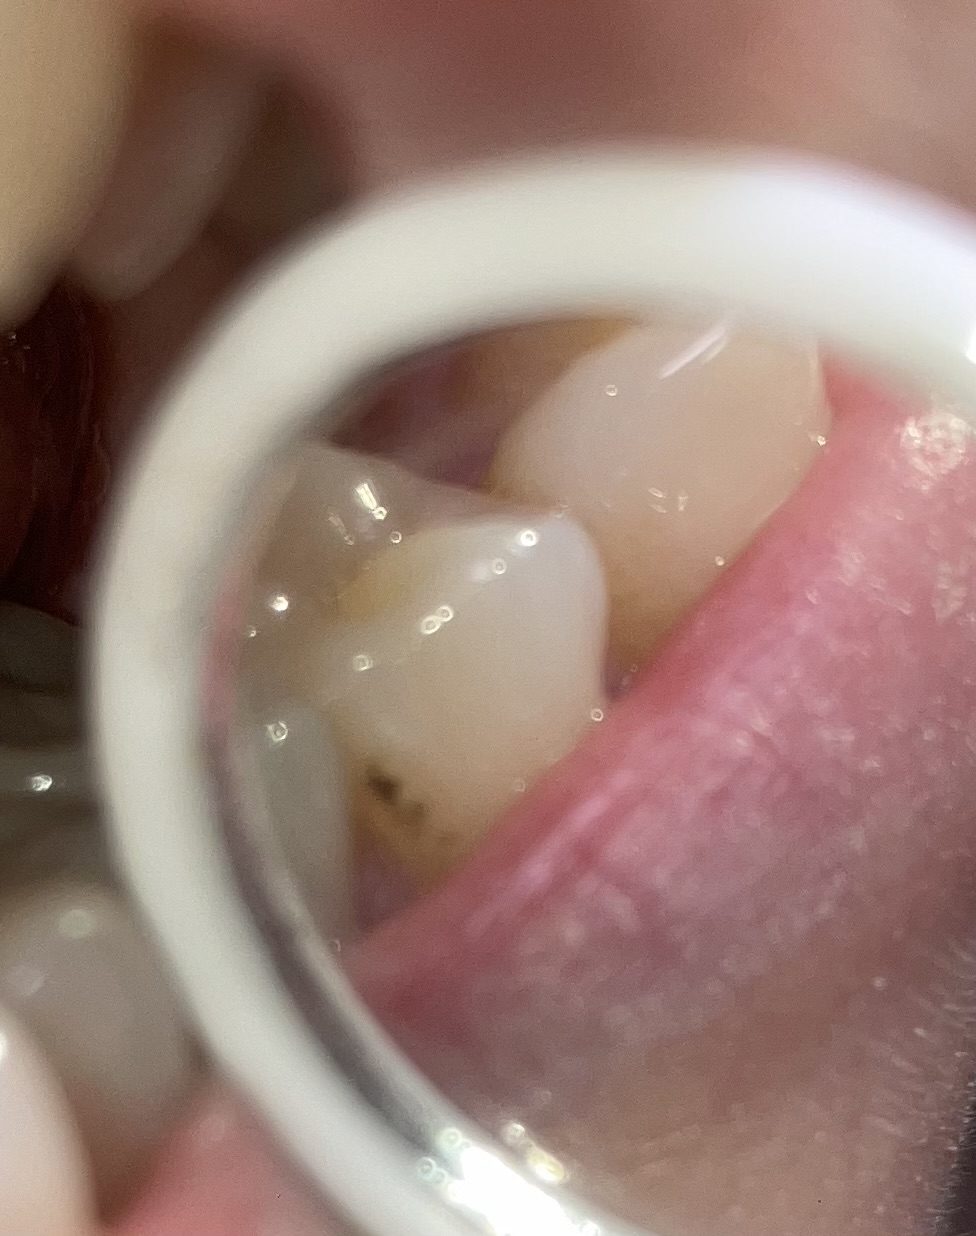

Niet een al te beste foto misschien, maar ik vraag me af of dit caries is bij de 35 (34 heb ik niet meer ivm beugel). Dit is een element zonder eerdere problemen. Het lijkt nu alsof daar bruin tussen zit - met spiegeltje geprobeerd een foto te nemen. Ik heb wat pijnklachten af en aan en maak me wat 'zorgen' erover. Moet ik er wat mee?

Duidelijk een verkleuring...een beginnend "gaatje". lijkt mij nog oppervlakkig maar zou moeten inspecteren om te zien of het door de glazuurgrens aangetast is zodat het gevuld moet worden. Indien u last heeft laten beoordelen of er wat aan gedaan moet worden. Zo op foto lijkt het alleen oppervlakkig en kan het wachten tot de volgende controle.